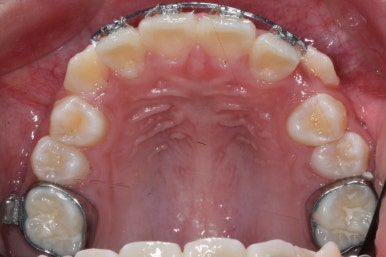

영구치도 이제 거의 다 나왔고 삐뚤한 다른 부분도 전체 메탈장치를 붙였습니다.

장치는 윗니부터 붙였습니다.

입안에 장치가 있다보니 불편할 수 있는데요. 이물감을 최소화 하고자 이동을 해야 할 양이 적은 아랫니들은 천천히 장치를 붙이기로 했습니다.

아래쪽에도 이제 장치를 전부 부착했습니다.

한 쪽의 송곳니는 제위치로 벌써 자리를 잡았네요.

장치를 부착한 후에 순차적으로 변화가 나타나는 모습입니다.

총 4장의 사진 동안 경과한 시간은 불과 6개월 입니다. 헤드기어를 통해 사전에 작업을 해뒀기 때문에 이후 연산동덧니교정 과정은 편해진 것이죠.

윗니만 6개월이 지난 모습입니다.

치열이 매우 가지런해졌죠. 이 후에는 특이사항 없이 종료가 되었습니다.